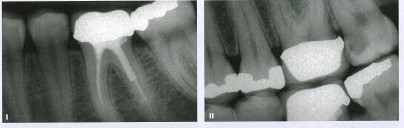

1、牙体预备量相对烤瓷较少,能够保持牙齿外形的完整,减少牙髓刺激。

(上图传统牙冠预备 磨牙量大)

(上图嵌体预备少,保留更多自己的牙体组织,龈上肩台)